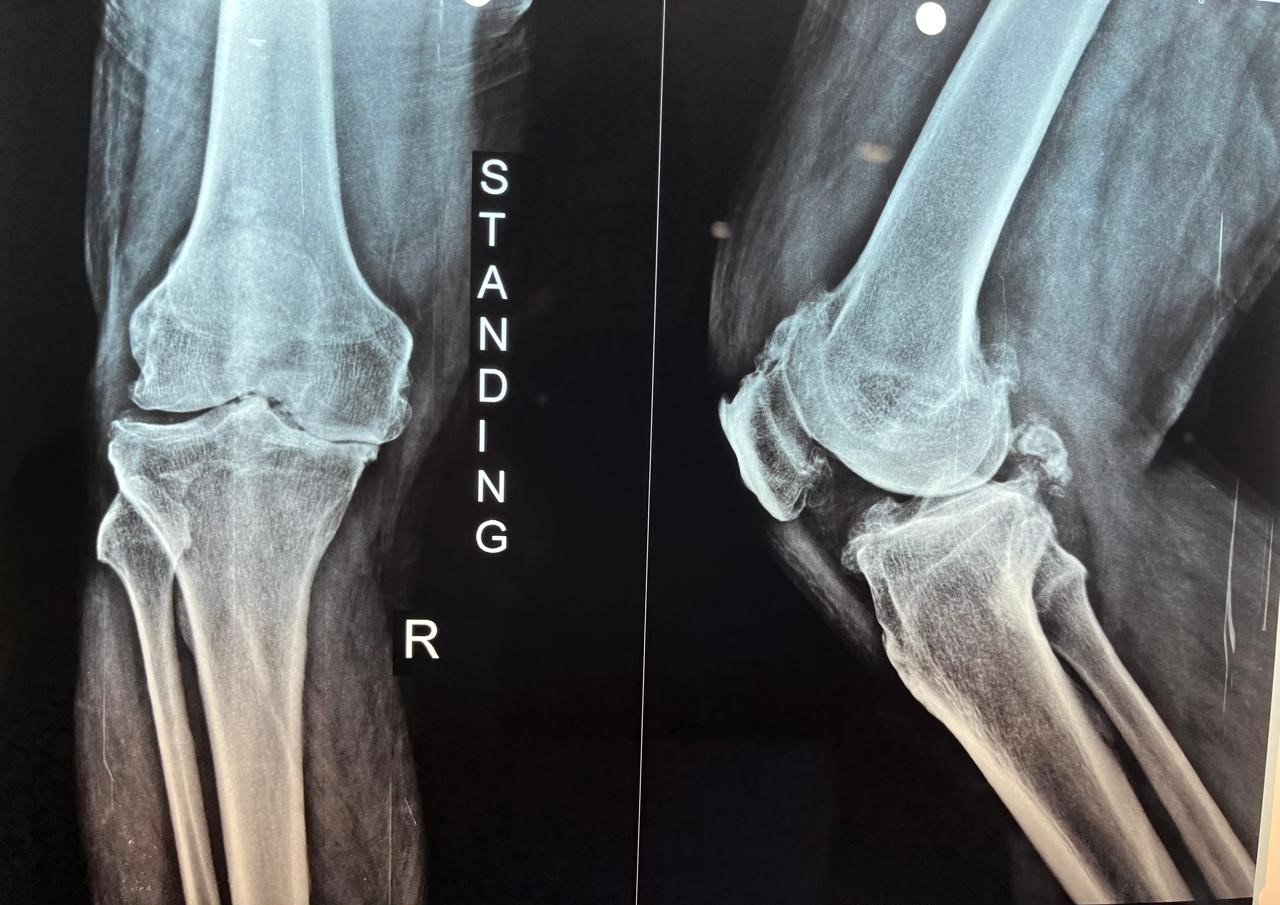

Pre-Op X-Ray

OA Knee with Fixed Flexion Deformity & Non correctable Varus